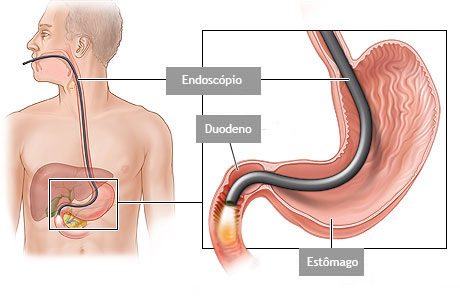

É um exame indicado para avaliação diagnóstica e tratamento das doenças da parte superior do tubo digestivo, incluindo o esôfago, o estômago e a porção inicial do duodeno.

Realizado introduzindo-se pela boca um aparelho flexível com iluminação central que permite a visualização de todo o trajeto examinado.

Com o paciente sedado, o aparelho é introduzido pela boca e passa através do esôfago e do estômago para o duodeno, local onde fica posicionada a papila duodenal.

É um exame indicado para avaliação diagnóstica e tratamento das doenças da parte superior do tubo digestivo, incluindo o esôfago, o estômago e a porção inicial do duodeno.

Realizado introduzindo-se pela boca um aparelho flexível com iluminação central que permite a visualização de todo o trajeto examinado.